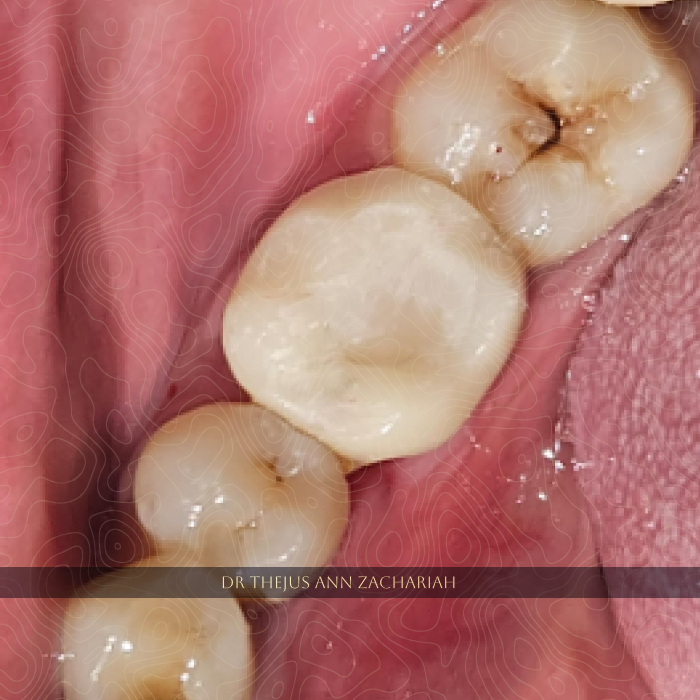

Post Endodontic Restoration By Crown Repair Protocol